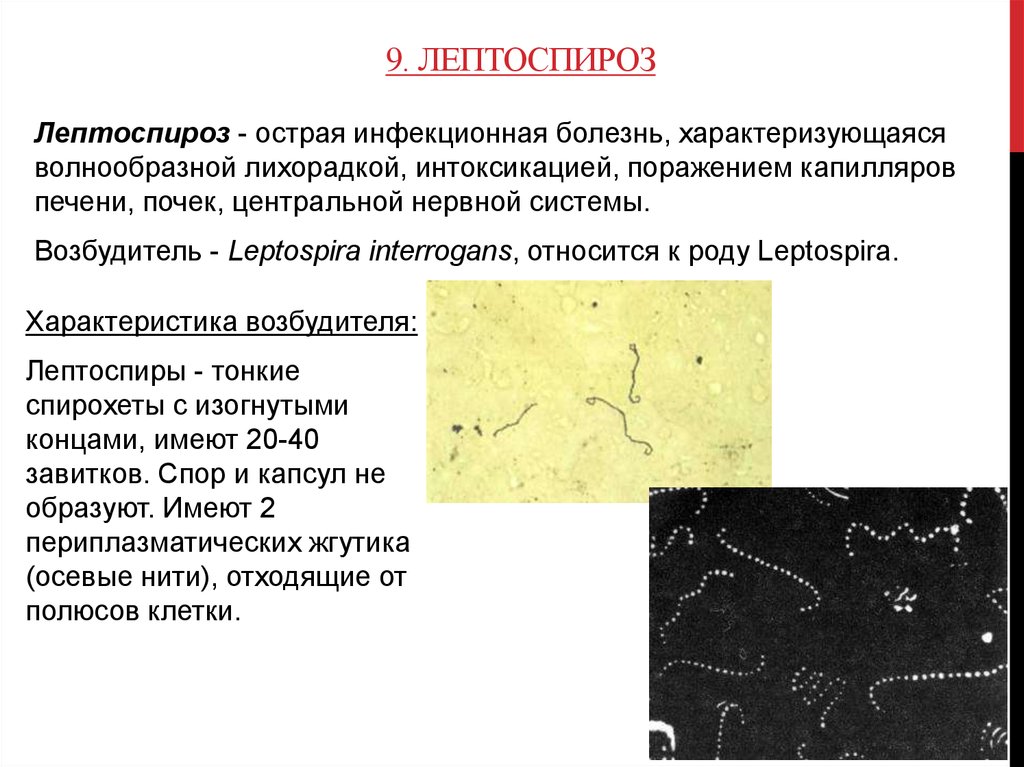

Лептоспиры: фотографии удивительных микроорганизмов